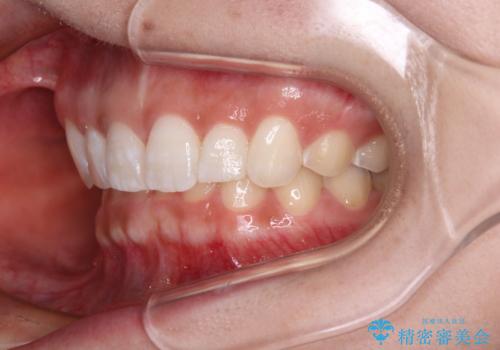

前歯のデコボコを治したい インビザライン矯正治療

- 前歯のデコボコ気になるとのことで来院された患者様です。

下顎骨が上顎骨に対して右側にシフトしており、さらに下顎が後方に位置しているため、非常に強い咬合力で食いしばっている状態でした。

上下顎ともに歯列全体の後方移動とIPR(歯と歯の間を削る)によってデコボコが解消するように設計し、インビザラインにより治療を行うこととしました。

強い咬合力による臼歯部の噛みにくさと、それに伴う歯の移動の鈍さに悩まされ、非常に長い期間を要することとなりました。

上下正中位置は、治療開始時よりは改善したものの、ここが限界であろうというところでのゴールとなりました。

下顎前歯の大半が隠れている状態ですが、左右への歯ぎしりはスムーズに行うことができ、就寝時には後戻り防止も兼ねて、食いしばり対策としてマウスピースの使用を継続するようお願いしております。